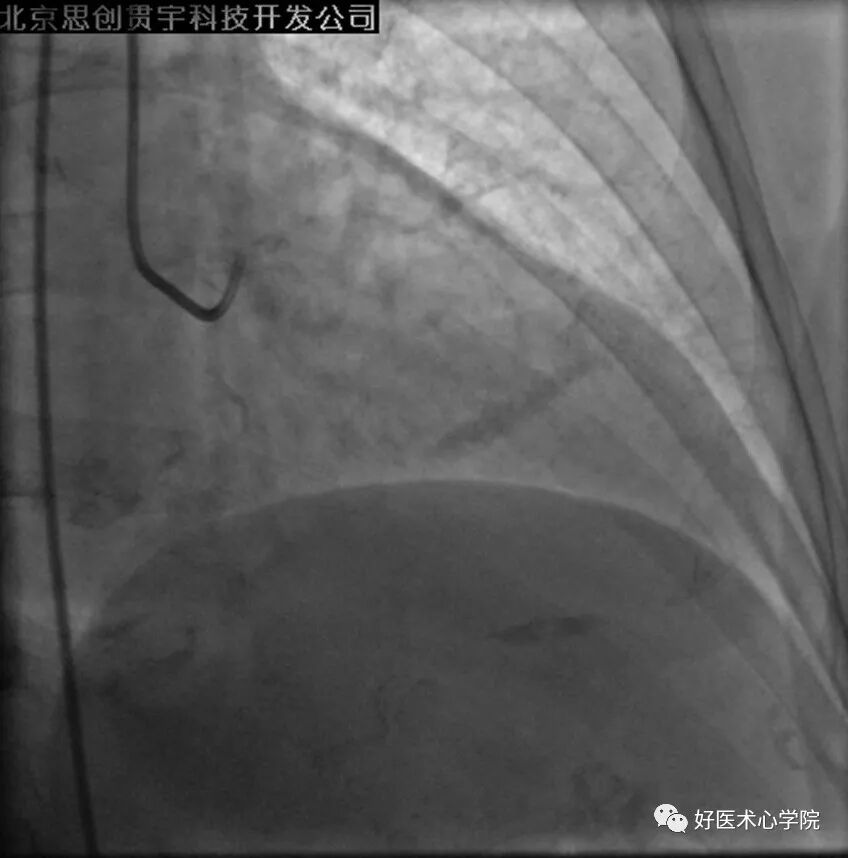

4. 冠脉痉挛(Coronary Spasm)

通常由器械诱发所致。 表现为表面光滑的狭窄节段,且远段冠脉节段无病变。

造影导丝是什么珍藏 冠脉造影从流程到诊断,基础必备!_https://www.jmylbn.com_新闻资讯_第87张

造影导丝是什么珍藏 冠脉造影从流程到诊断,基础必备!_https://www.jmylbn.com_新闻资讯_第88张